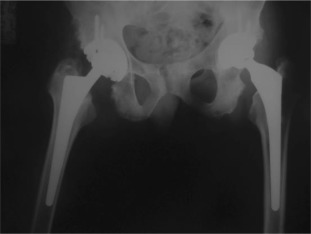

Pre-operative x-ray of a patient with bony ankylosis.

Fig. 1.

There were 61 patients (50 male, 11 female) with 105 affected hips (72% bilateral, 28% unilateral). The average patient age at surgery was 41.3 ± 10.2 years old. The age of patients at THA was as follows: <30 years for 14 patients (23 hips), 31–50 years for 41 patients (73 hips) and >50 years for 6 patients (9 hips) (Graph 1 ). The younger age at diagnosis (<30 years old) of AS was correlated with younger age at THA (p < 0.05). Bone ankylosis was detected in 37 (35%) and acetabular protrusion was noticed in 18 (17%) hips in pre-operative radiographs (Fig. 1 , Fig. 2 , Fig. 3  ;  Fig. 4 ) (Table 1 ). The mean pre-operative flexion contracture was 20.3°±21.8°. In patients without ankylosis, the mean total hip range of motion (ROM) was 67.8°±25.7°.